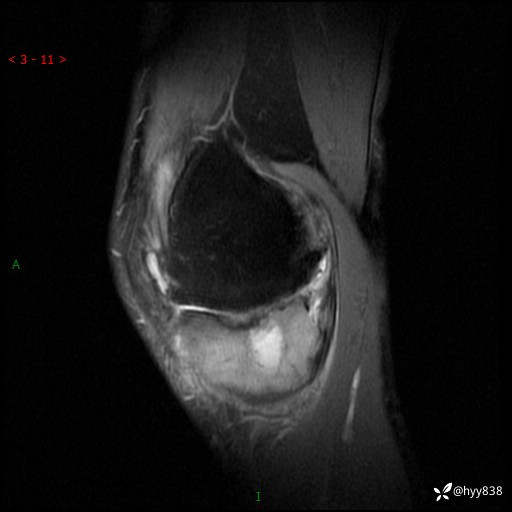

CT

干骺端溶骨性病变病灶周广泛水肿

脓肿

骨母